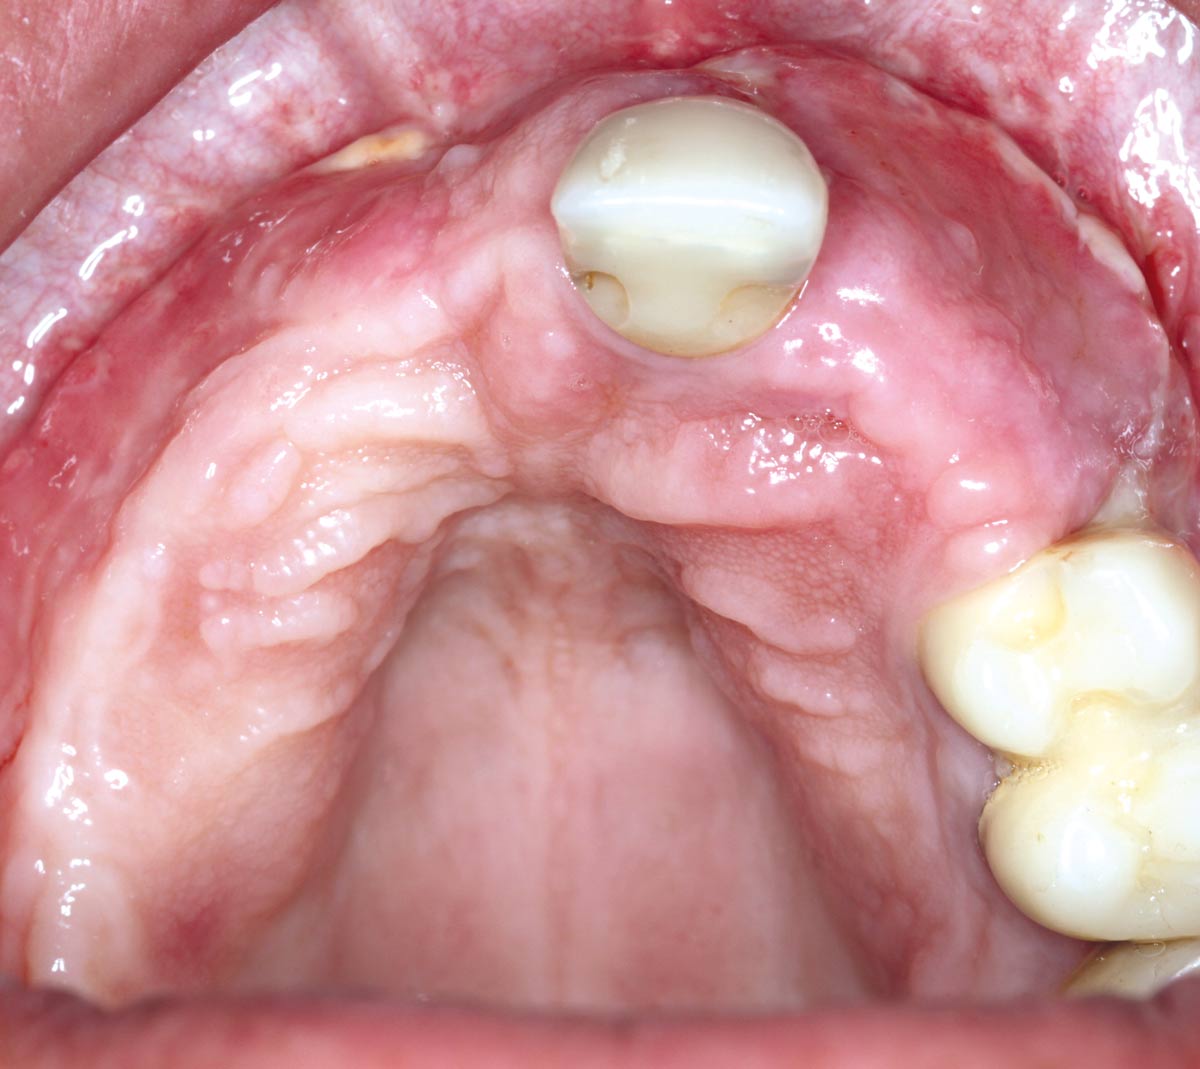

Clinical situation: 71-old patient with atrial fibrillation and Warfarin medication